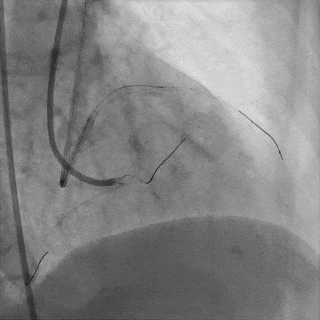

双侧造影,观察闭塞起始位置、长度、走行等

尝试通过RCA-圆锥支侧枝逆向开通LAD :

微导管辅助下,用SUOH03导丝尝试送入侧枝

经微导管TIP injection可见侧枝重度迂曲

侧枝重度迂曲,反复尝试未能通过